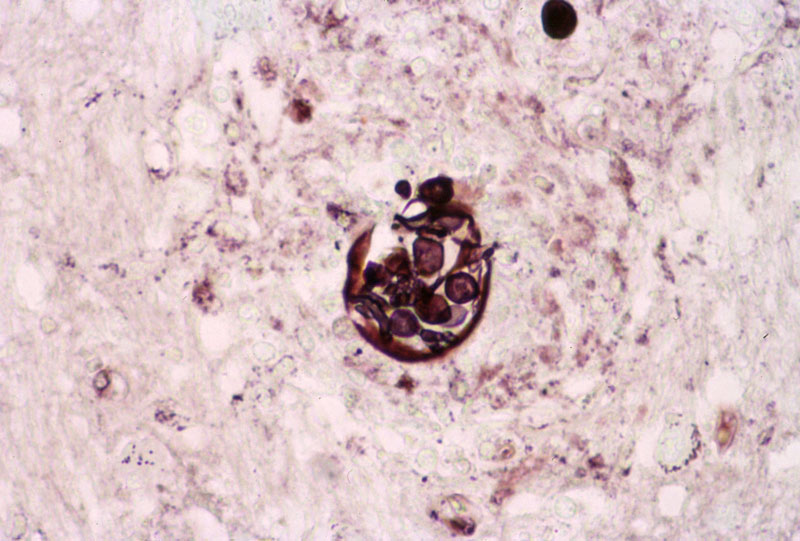

PAS stain

High magnification PAS stain image: In contrast, the outline of cell wall can be well highlighted by periodic acid Schiff (PAS) stain as illustrated in these images. In this case, most of the fungal organisms do not contain viable endospores which may be resulted from prolonged antifungal therapy. However, one of the funcal organisms containing spores may be present in the PAS stain (arrow).

Hematoxylin & eosin

Gomori's methanamine silver (GMS)

Image from another case: In this case of infection of the brain parenchyma, the small spores within a spheres can be well see on hematoxylin and eosin stain (arrow) and are well demonstrated by GMS stain. Note that there is also no giant cell reaction in this case.